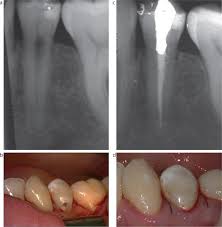

Before and After Images

Our Root Canal Treatment Experiences

Root Canal Therapy

X-rays are taken to determine the extent of the damage. Local anesthesia is administered to numb the area.An opening is made in the crown of the tooth to access the pulp.The infected or damaged pulp is removed, and the root canals are cleaned and shaped The cleaned canals are filled with a biocompatible material, usually gutta-percha.